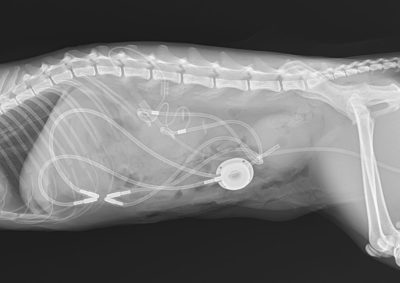

SUB Systems